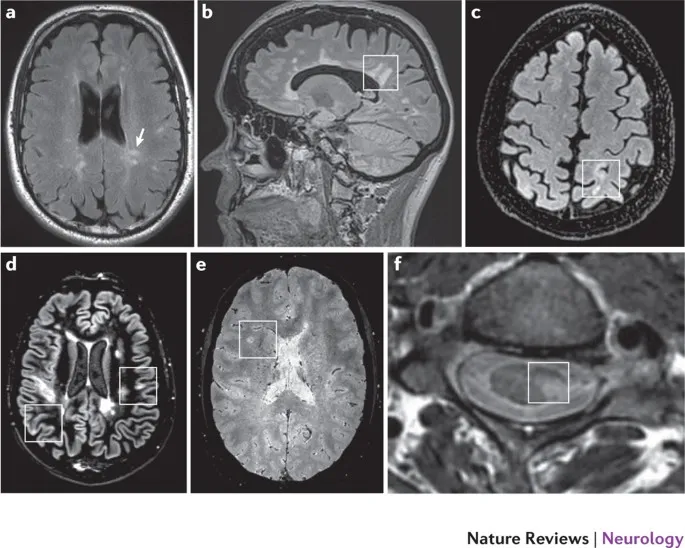

⭐ In MS, MRI reveals characteristic demyelinating plaques, often in a periventricular distribution.

- Periventricular white matter (Dawson's fingers)

⭐ High-Yield: Plaques often have a characteristic ovoid shape and are oriented perpendicular to the lateral ventricles, following the path of deep medullary veins. This is the basis for the classic "Dawson's fingers" sign on sagittal MRI.